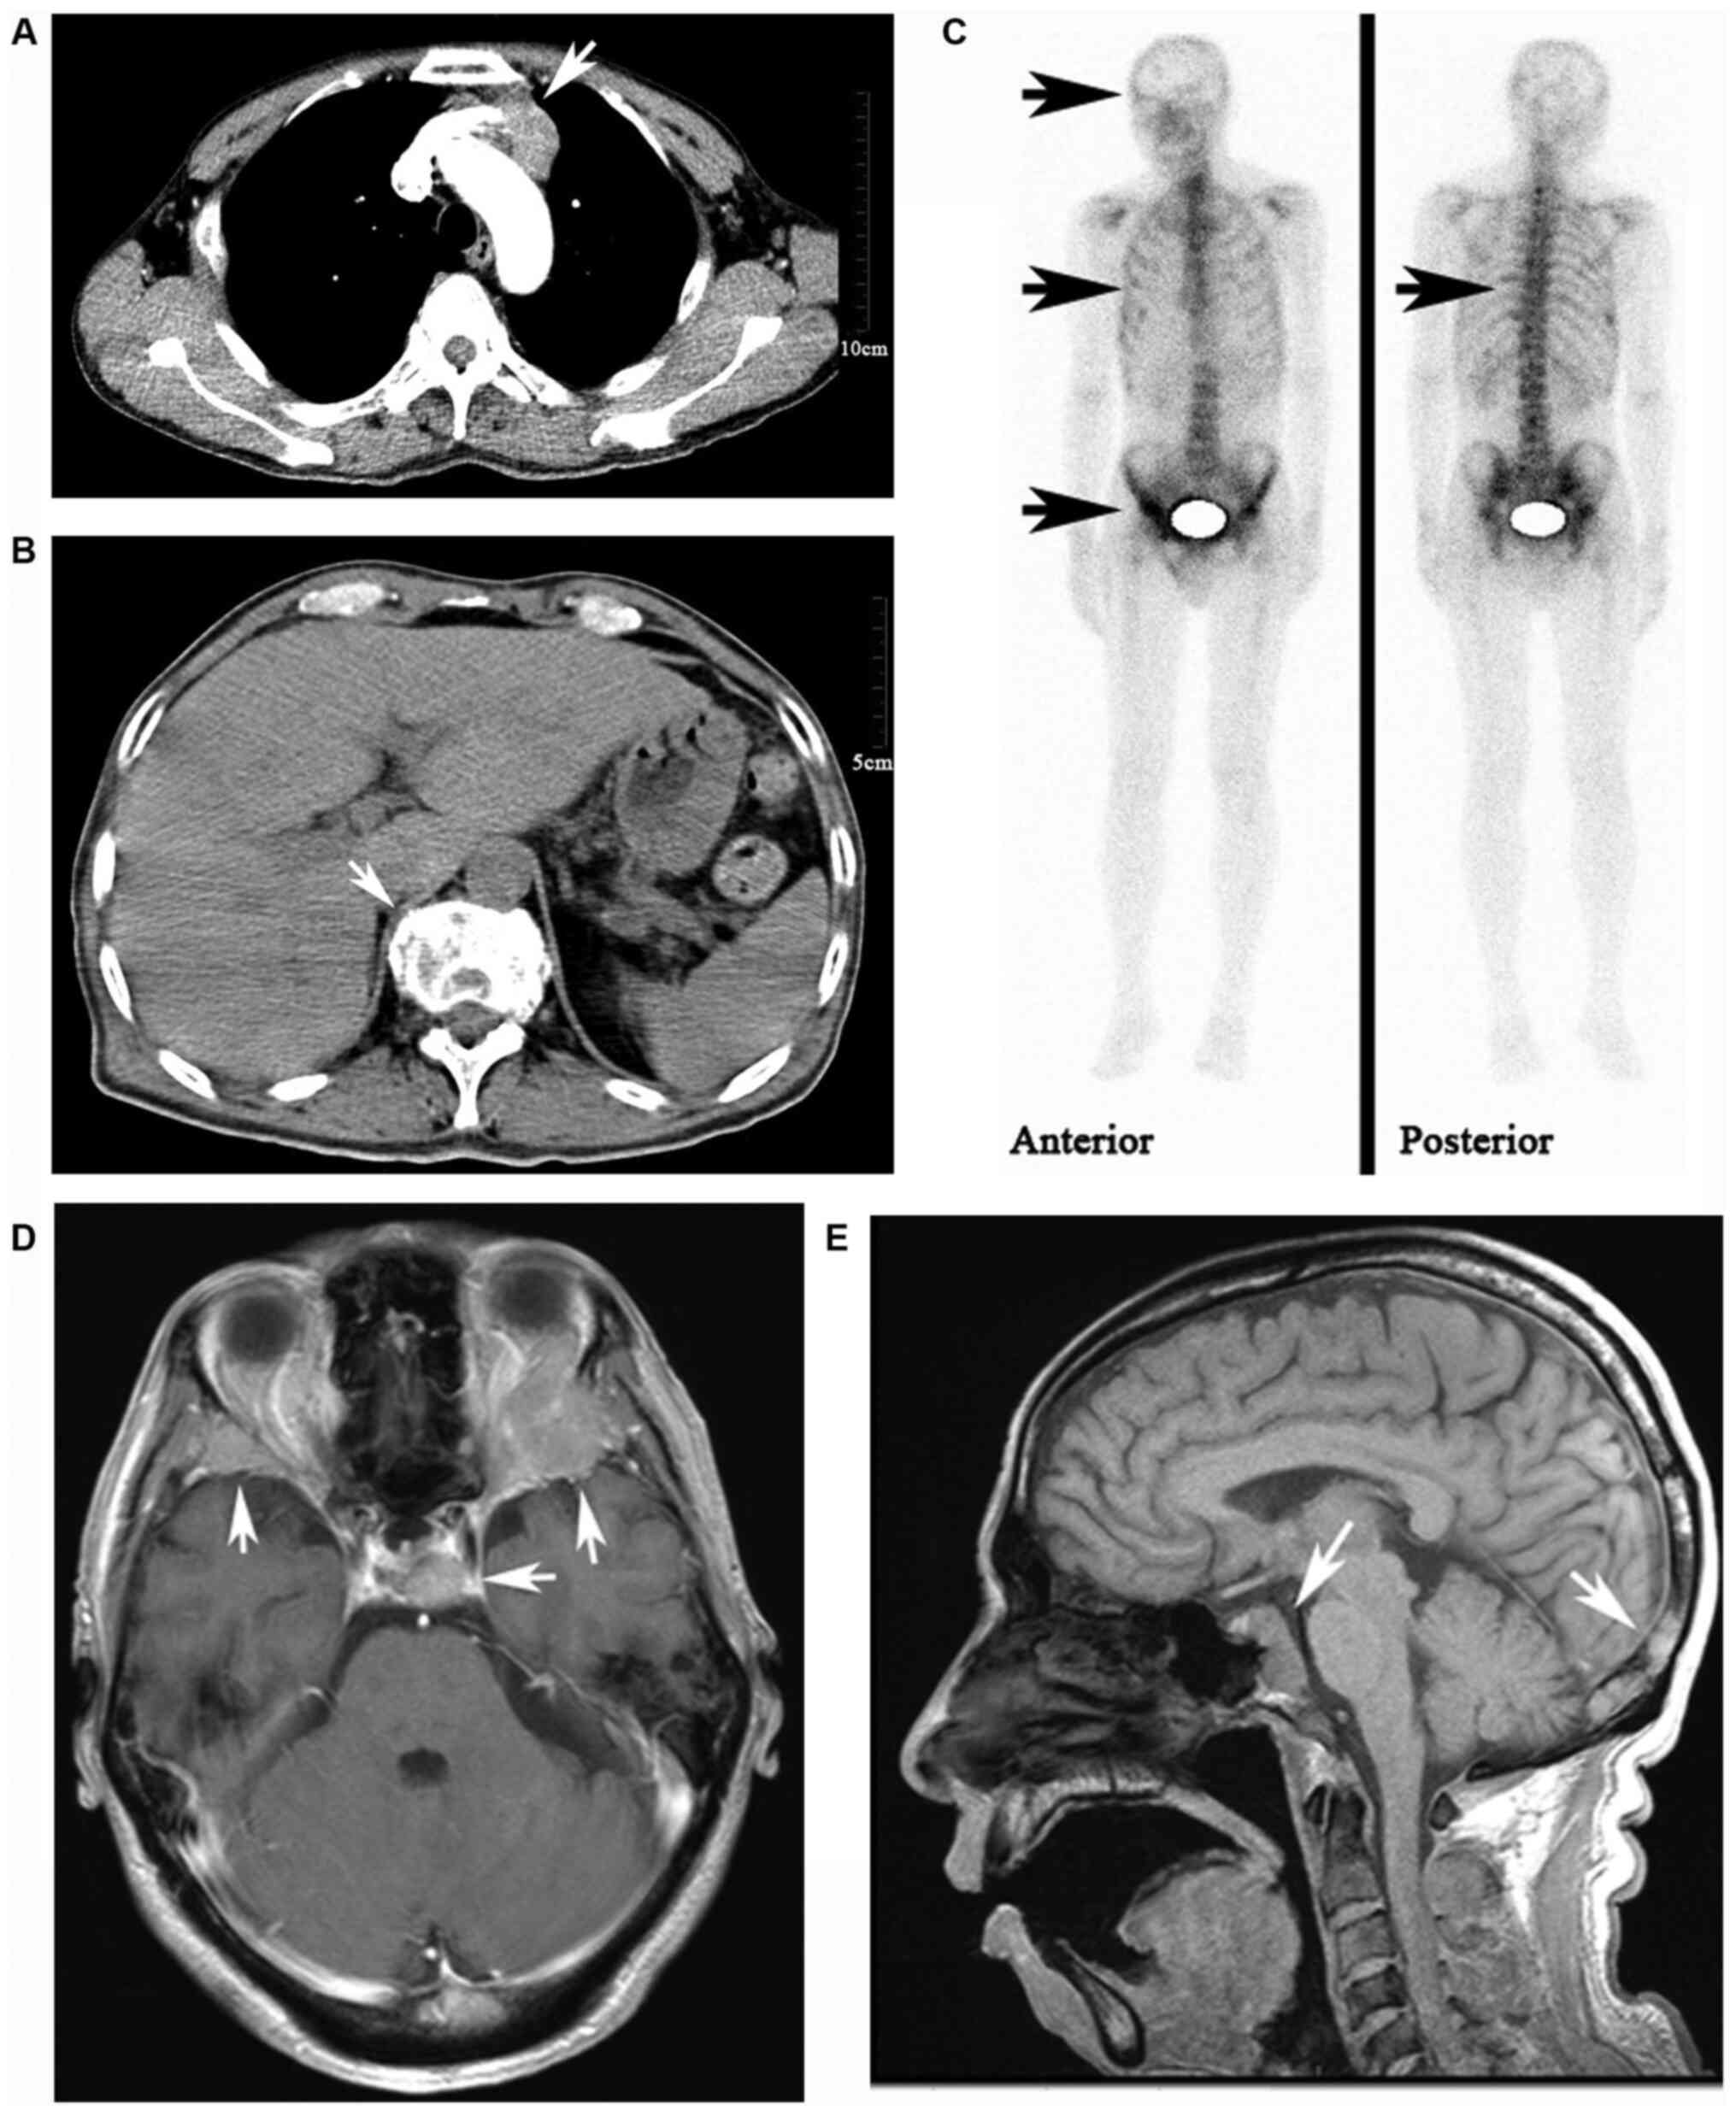

Primary Thymic Atypical Carcinoid With Rare Multiple Bone Metastasis A Case Report And Literature Review